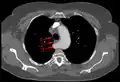

- Aberrant subclavian artery at axial CT-scan. (1) trachea, (2) esophagus, (3) Aberrant subclavian artery.